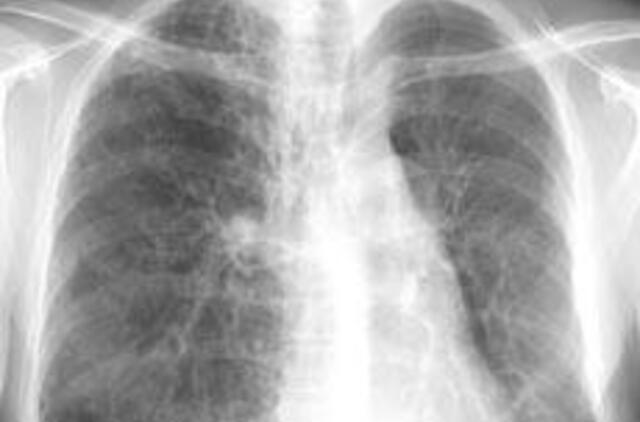

Kauno medicinos universiteto klinikose (KMUK) atlikta itin sudėtinga plaučių transplantacijos operacija. Tai tik trečioji tokia operacija Lietuvoje. Plaučiai persodinti 52 metų amžiaus vyrui, kuris į transplantacijos operacijos laukiančiųjų sąrašą dėl lėtinės plaučių ligos ir kvėpavimo funkcijos nepakankamumo

buvo įtrauktas prieš 3,5 mėnesio.